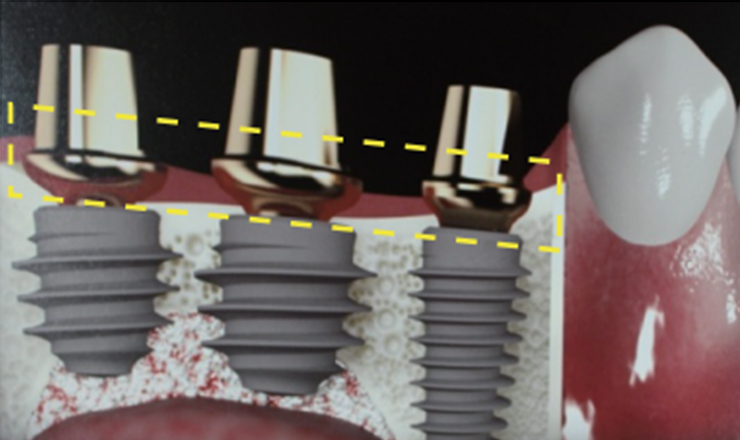

Abutment (지대주)

임플란트 뿌리와 머리를 연결하는 부위입니다.

기성 어버트먼트 VS 맞춤 어버트먼트

기성 어버트먼트와 커스텀 어버트먼트 비교

기성 Abutment

기성 Abutment1잇몸과 보철물 사이에 들뜨는 공간으로 음식물 끼임 현상이 생깁니다.

(잇몸염증 유발)2보철물의 안쪽 공간에 비해 얇은 지대주가 저작력을 분산 시키지 못해 보철물이 깨질 위험이 있습니다.

맞춤형 Abutment

맞춤형 Abutment1보철물과 잇몸 사이 들뜨는 공간이 없어 음식물 끼임이 적습니다.

(잇몸염증 예방)2보철물과 지대주 사이의 빈 공간이 적어 분산되지 않은 저작력에 의해 보철물이 깨질 위험이 적습니다.

심다치과 커스텀 어버트먼트

심다치과의 개인 맞춤형 지대주

저희 심다치과 지대주(어버트먼트)는 자연치아의 지대치 형태와

최대한 유사하게 제작되어 도재(보철물) 파절과 임플란트 주위염을 최소화 합니다.